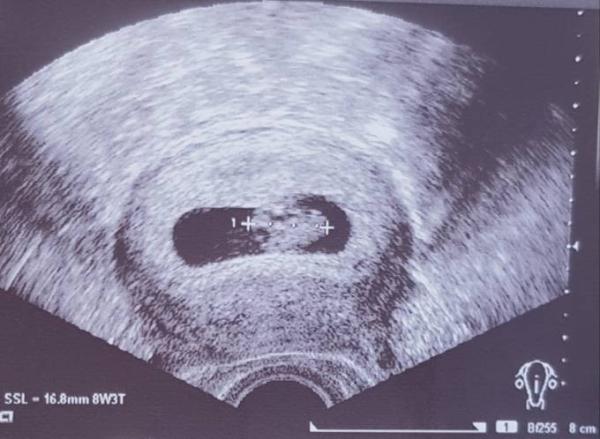

Hallo ihr Lieben! Wir waren heute beim FA und haben das kleine Herzchen pochen sehen und haben uns sofort total verliebt! Das kleine Würmchen ist schon 16,8mm groß und wir sind absolut glücklich...aber wie das immer so ist, entdeckt man immer was, was einem Angst machen kann Ist es normal, dass die Fruchthöle länglich und nicht rund ist... irgendwie macht mir das gerade Sorgen. Es ist unser erstes Kind und ich hab davon echt keine Ahnung... beim Arzt hatte ich auch kein ungutes Gefühl, sodass ich nicht gefragt habe...ist mir da gar nicht aufgefallen...dafür jetzt umso mehr. Zudem bin ich 7+4 laut Rechner, aber da steht 8+3 ??!! Da freut man sich so auf das Bild und dann wird man kirre :D

Die Form der Höhle kommt vom Winkel beim schallen. Die sieht nicht "in echt" so aus Und der Computer im US-Gerät errechnet automatisch anhand der Messdaten ein Gestationsalter. Das hat nicht viel zu sagen. Alles gut, solange die Differenz nicht zu groß ist. Sind ja nur 6 Tage. Alles tutti, freu dich einfach